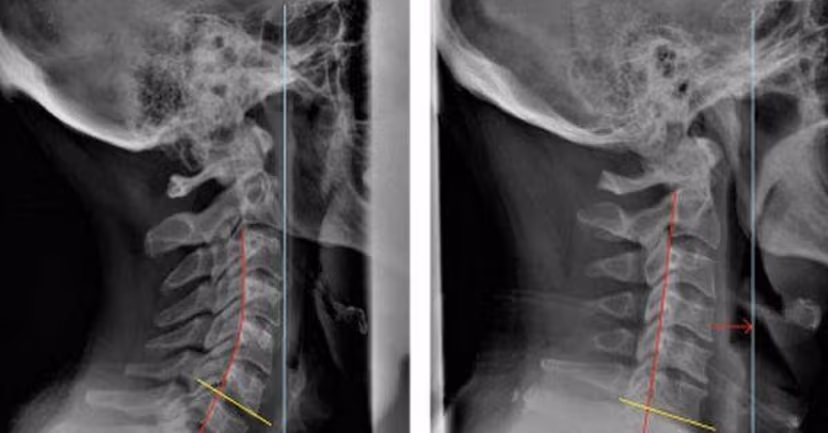

Đốt sống cổ (cột sống cổ) là nhóm xương khớp được ghép lại với nhau bởi 7 đốt sống đầu tiên của cột sống, uốn hình chữ C và được ký hiệu từ C1 đến C7.

Tình trạng vận động và tổn thương kéo dài có thể làm cho cột sống cổ bị suy giảm chức năng và dẫn đến thoái hóa. Thoái hóa đốt sống cổ thường bắt đầu từ những tổn thương khớp ở thân đốt, đĩa liên đốt, các màng, dây chằng,… Các đốt sống hay gặp thoái hóa nhiều nhất đó là ở các vị trí C4, C5 và C6.

Thoái hóa ở các đốt sống này thường gây cứng cổ, khiến cổ hoạt động không linh hoạt. Người bệnh thường cảm thấy đau khớp cổ, nhất là khi vận động vùng này. Đau có thể lan dần xuống vai. Đôi lúc bệnh nhân có thể đau đầu không rõ nguyên nhân… Thoái hóa cột sống cổ gây nhiều khó khăn cho người bệnh trong sinh hoạt và lao động. Đáng lo khi bệnh ngày càng trở nên phổ biến và có xu hướng trẻ hóa.

Thoái hóa, thoát vị đĩa đệm, gai các đốt sống vùng cổ có thể dẫn đến đau nhức, hạn chế vận động cổ.